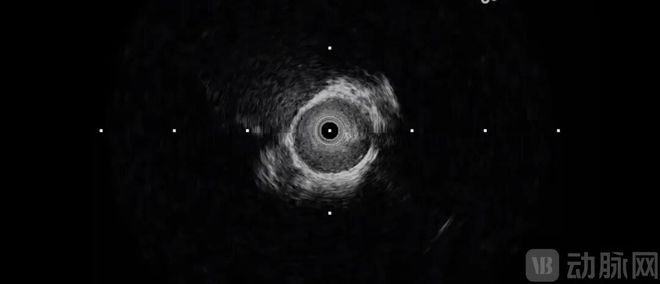

作为专为颅内血管优化的腔内影像技术,Neuro-IVUS搭载了0.42mm×0.53mm的超微型超声换能器(约头发丝直径的二分之一),成功突破了传统IVUS导管无法进入2mm脑血管的物理极限;其首创的AI抗干扰算法可有效过滤颅骨伪影,实现在4-8mm穿透深度下的高分辨率成像,攻克了“只见管腔、不见管壁”的影像盲区,填补了全球脑血管内超声诊疗技术的空白。

超微型高频探头,突破尺寸极限。鑫云生科研发出0.42mm×0.53mm的超微型超声换能器(约为头发丝直径的一半),搭配0.57mm-0.9mm直径导管,可深入2mm级脑血管。其50MHz超高频设计可实现4-8mm穿透深度的高清成像,连0.1mm的薄纤维帽也能清晰识别,可精准评估钙化灶分布等微观病变。